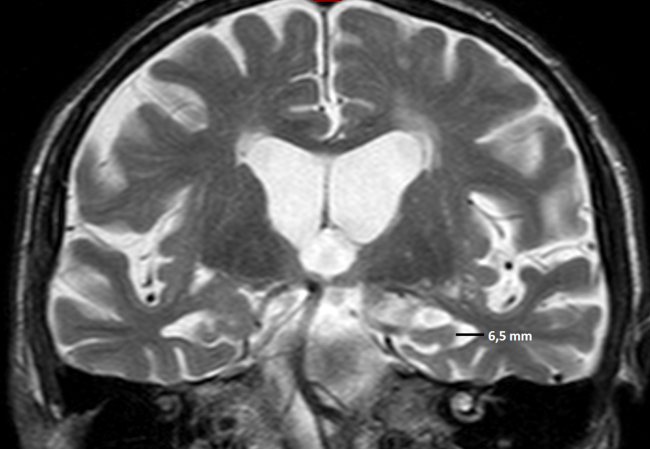

La RM es la modalidad de elección, prefiriéndose los cortes sagitales para la medición, ya que en los coronales se dificulta la visualización de los límites del agujero Magno.17

La medida debe tomarse trazando una línea recta entre el basión y el opistión del agujero Magno. Luego se traza una línea perpendicular a la primera, hasta el extremo distal de la amígdala herniada (►Fig. 3).

Existe disenso entre los estudios de cohorte en relación al valor exacto en milímetros del descenso amigdalar. La ►Tabla 1 resume las medidas del descenso amigdalar según el grupo etario.20

Existe relación entre el grado de descenso amigdalino y la presencia y grado de sintomatología,17 descensos menores a 10 mm suelen no dar síntomas.19